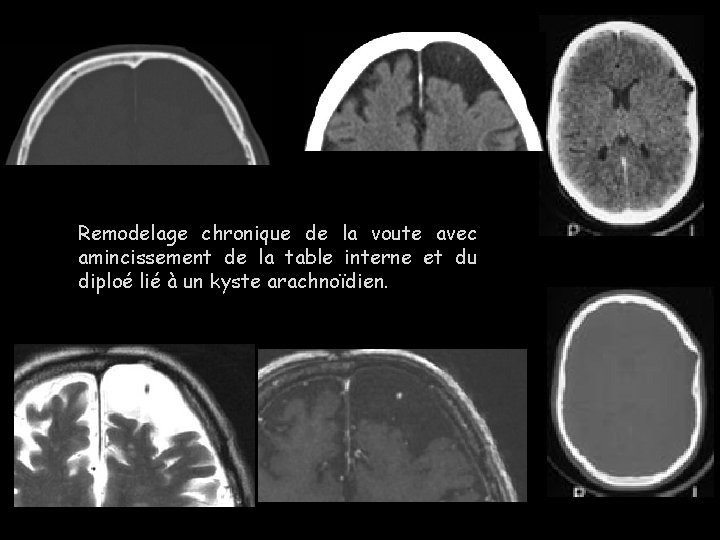

Remodelage chronique de la voute avec amincissement de la table interne et du diploé lié à un kyste arachnoïdien.

IRM T 1: volumineux kyste arachnoïdien à l’origine d’un discret effet de masse sur les structures médianes et d’un amincissement marqué de la table interne frontotemporale gauche, également déformée.